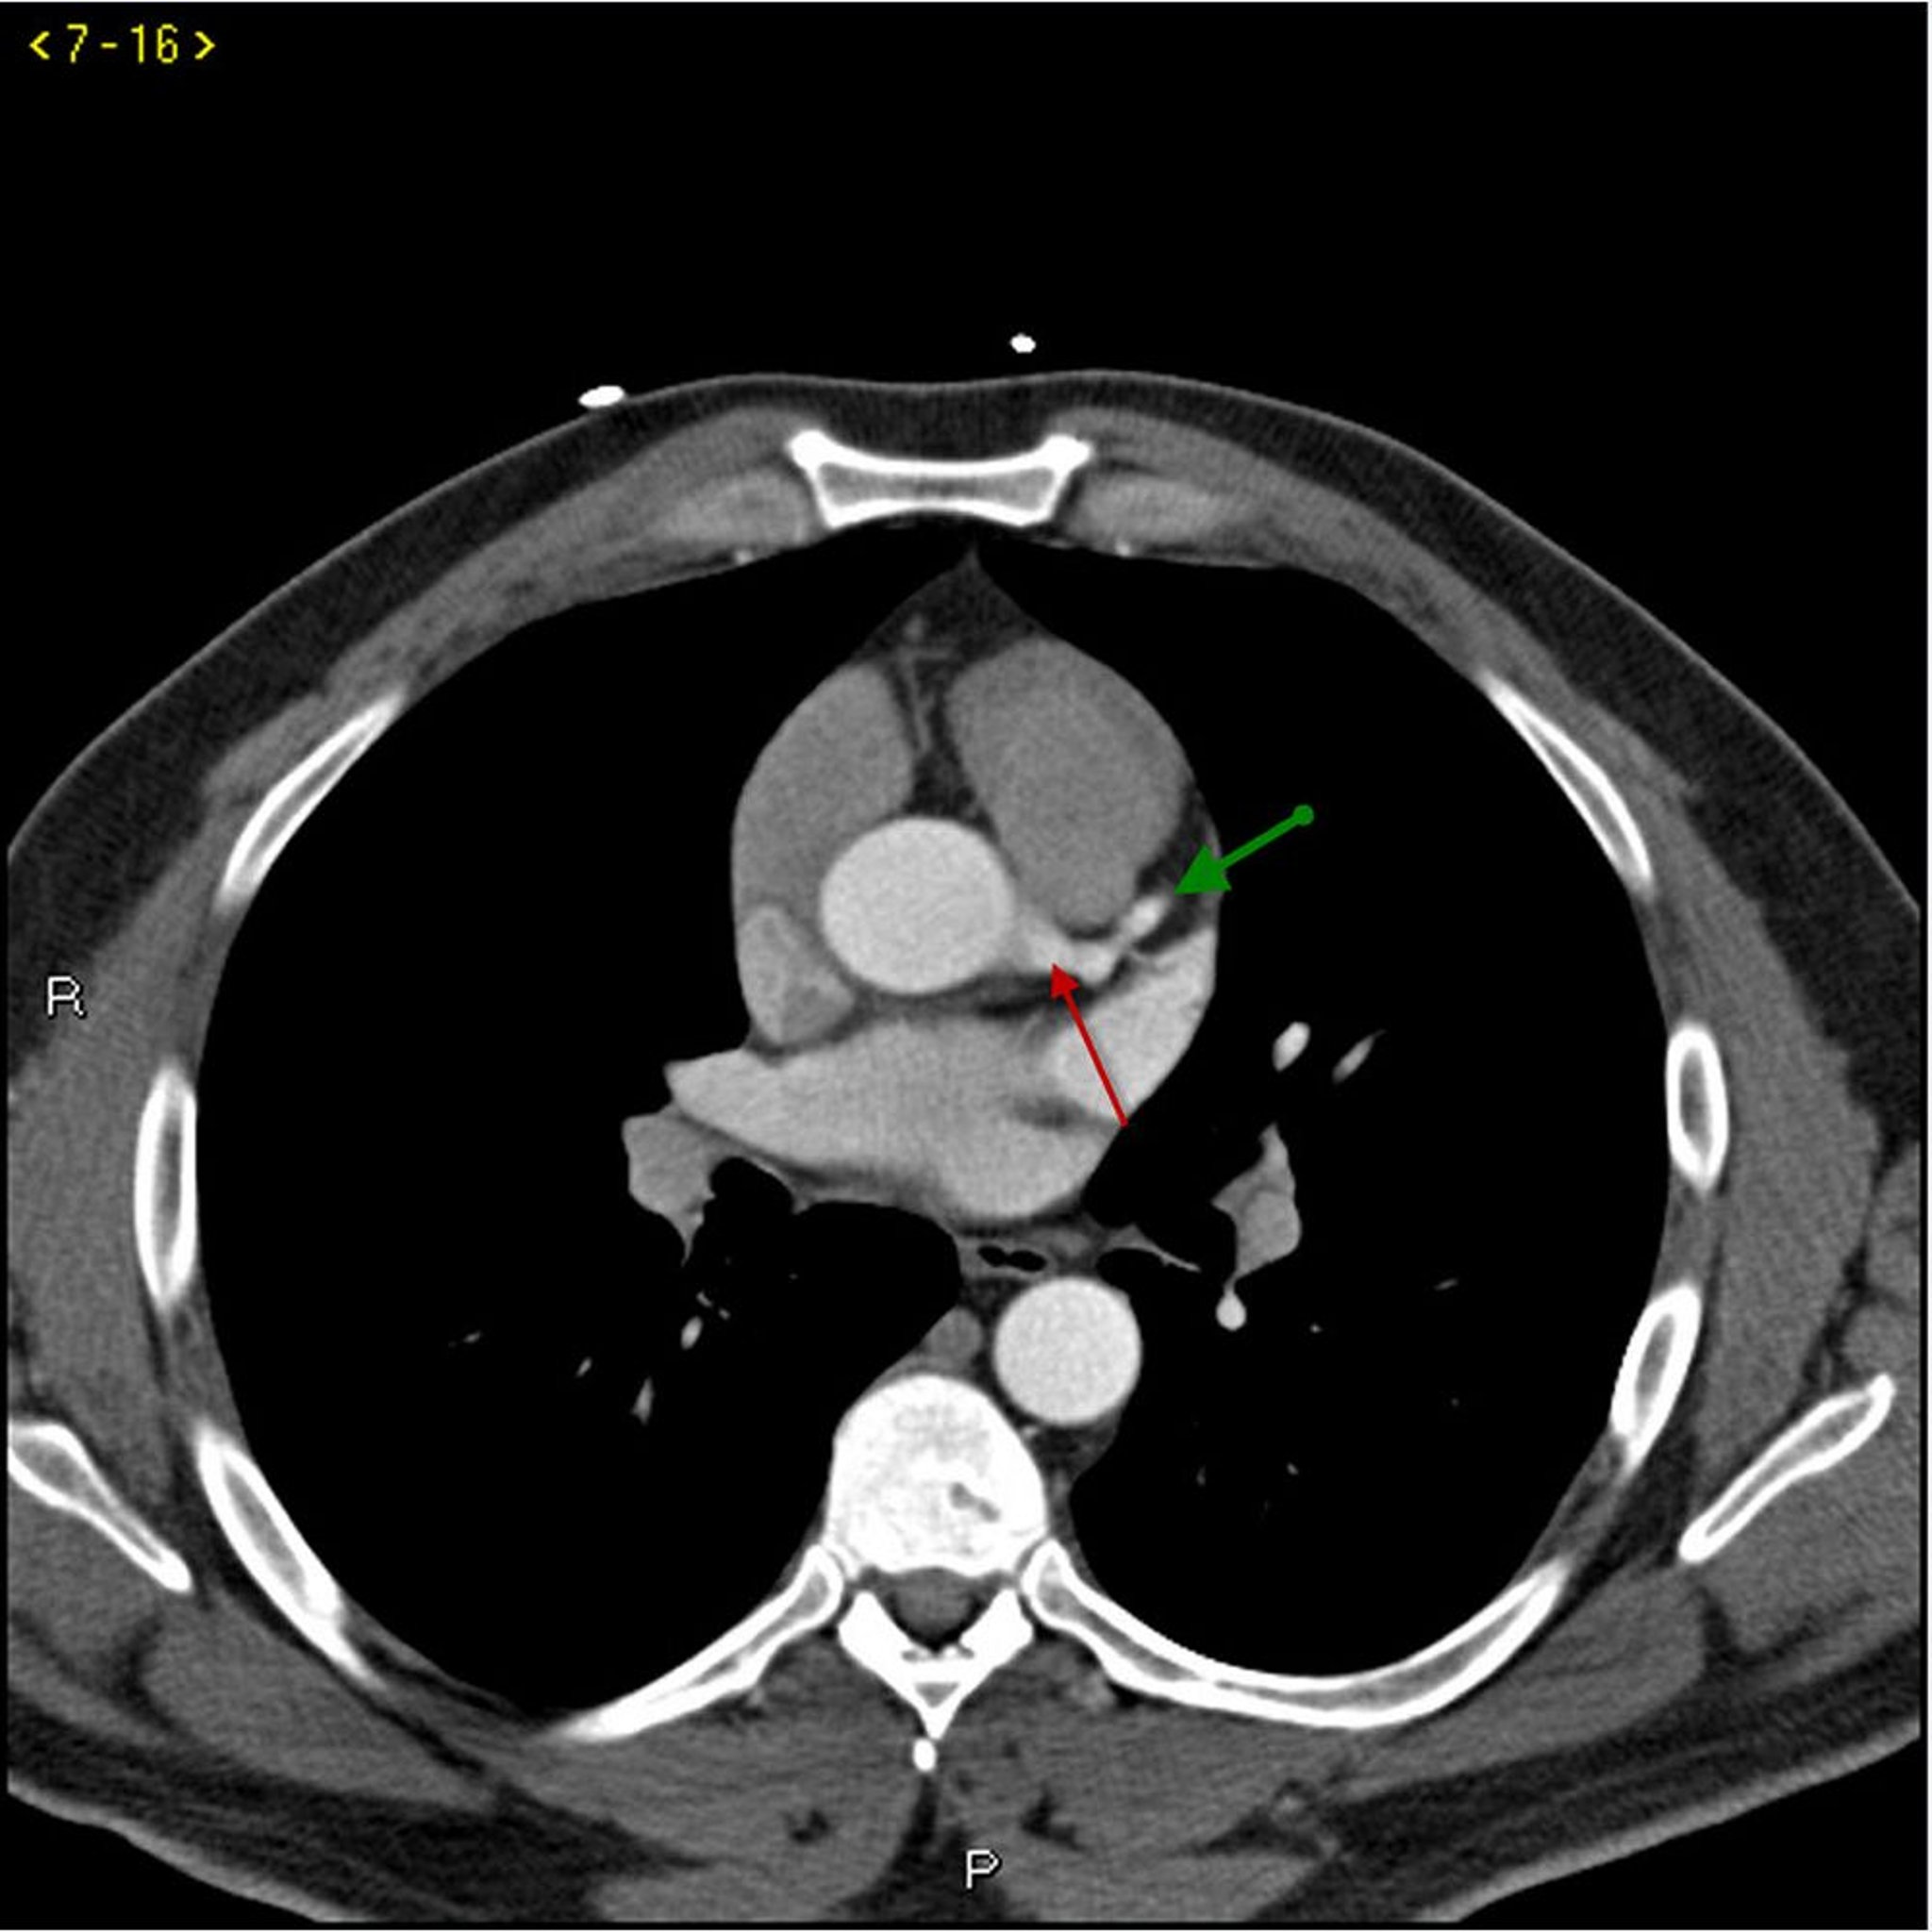

TC com contraste mostrando artérias coronárias normais – Diapositivo 1

Essa TC com contraste mostra artérias coronárias normais. A artéria esquerda principal é indicada pela seta vermelha. As artérias descendente anterior esquerda e circunflexa esquerda são indicadas pelas setas verde e azul, respectivamente, e a artéria coronária direita é indicada pela seta roxa.